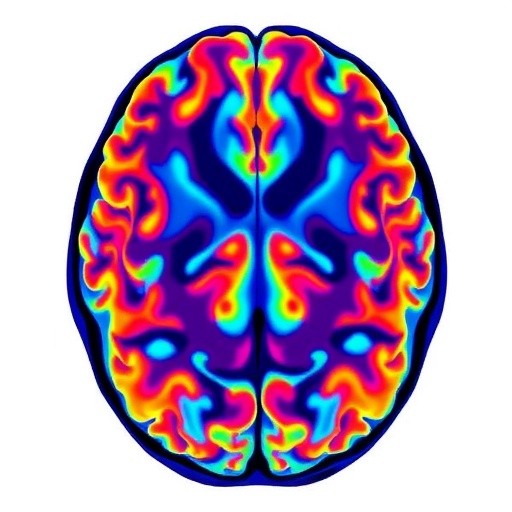

The study harnesses advanced neuroimaging techniques, leveraging cutting-edge diffusion tensor imaging (DTI) methods that allow unprecedented visualization of brain microstructure. These imaging modalities measure the diffusion of water molecules in brain tissue, providing indirect yet highly sensitive markers of axonal integrity, myelin density, and microstructural complexity. By applying these tools, researchers have demonstrated subtle yet statistically significant alterations in white matter tracts connecting critical cognitive hubs in Parkinson’s patients with subjective cognitive complaints.

One remarkable aspect of the findings is the identification of microstructural deteriorations in the frontostriatal circuits, which are crucial for executive functions, attention, and working memory. The frontostriatal pathway is a neural network well-known for its role in motor control but equally indispensable for cognitive processing. Decline within these tracts may explain the early cognitive symptoms experienced by patients even before measurable deficits surface in standard cognitive assessments.

Additional disruptions were noted in the limbic system, especially within white matter pathways linked to the hippocampus and amygdala. These regions are traditionally associated with memory consolidation and emotional regulation. The imaging evidence suggests that the neurodegenerative footprint of Parkinson’s disease extends beyond classic motor circuits, potentially involving networks fundamental to mood and memory processing long before overt dementia develops.

Among the most compelling technical achievements in this work was the integration of multi-shell diffusion imaging with advanced modeling algorithms. These methods allowed researchers to disaggregate various tissue compartments and characterize microstructural features such as neurite orientation dispersion and density. This granularity surpasses older DTI techniques that offer only aggregate measures like fractional anisotropy, enabling a more nuanced understanding of brain tissue pathology at the microscopic level.